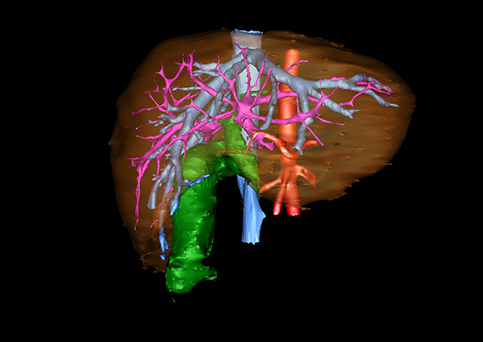

10、三维重建虚拟肝脏、胆道显像技术

三维虚拟肝脏技术是在二维影像学资料如CT等图像的基础上,通过三维重组软件和工具,比如青岛大学附属医院与海信医疗集团联合自主研发的海信计算机辅助手术系统(Hisense Computer Assisted Surgery,Hisense CAS),目前已投入临床并指导实际应用,利用该类系统对二维影像学的数据资料进行三维立体分析,重组形成立体的、有空间结构的、虚拟的肝脏三维图像。这项技术较传统的二维平面成像技术,有着明显的优势,3D虚拟肝脏技术可以构造出一个虚拟的、可视化的肝脏模型。通过对这种模型的观察,可以很容易地分辨出肝脏器官的组织结构、解剖特点,直观研究肝外胆总管的形态差异,明确肝内胆管的形态、走形、是否合并扩张、狭窄及结石,胰胆管合流的形态及共同通道内是否有狭窄、扩张和结石等病变情况,预先规划处理可能合并存在的肝内胆管扩张、狭窄或其他复杂胆道畸形,清晰地显示肝内脉管系统,包括门静脉、肝动脉及肝静脉的走行、分支,并可多角度、全方位观察病变胆道与其周围重要血管尤其是伴行的门静脉之间的解剖关系,大大提高了外科医师在术前对肝脏内部各管道结构及其变异判断的精确性和可靠性,精准地对病变进行判断和评估,还可根据患者自身的病变特点,制定出合理、个体化的手术方案,最大限度地降低术中和术后并发症发生率,并术中导航实时指导手术,提高手术的精准性和成功率。

图12:先天性胆管扩张症梭状型合并左右肝管分别汇入胆总管囊肿三维重建虚拟肝脏、胆道显像

a 图为术前二维CT图像;b 图为CT经多平面重组技术(MPR)所得的三维重建图像,可粗略地判断病变胆管的位置;c 图为MRCP显示胆总管梭状扩张;d 图为术前Hisense CAS三维重建显示胆管的分布走形及其与肝内三套血管系统的解剖关系;e 图为胆道系统立体形态及与肝脏整体的空间关系,箭头处显示对于左右肝管分别汇入胆总管囊肿中,整个肝总管也明显扩张而成为囊肿的一部分。术前规划为先将囊肿完全切除,左右肝管合并成形后再与空肠吻合。